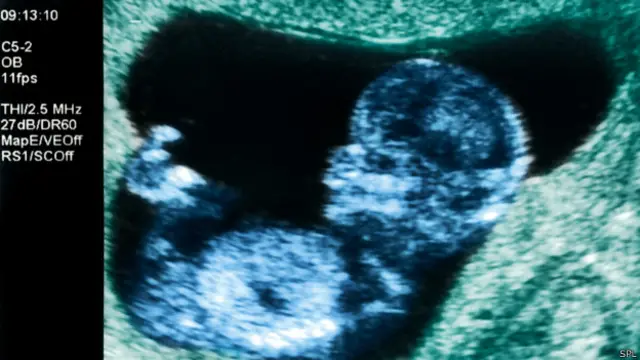

Автор фото, SPL